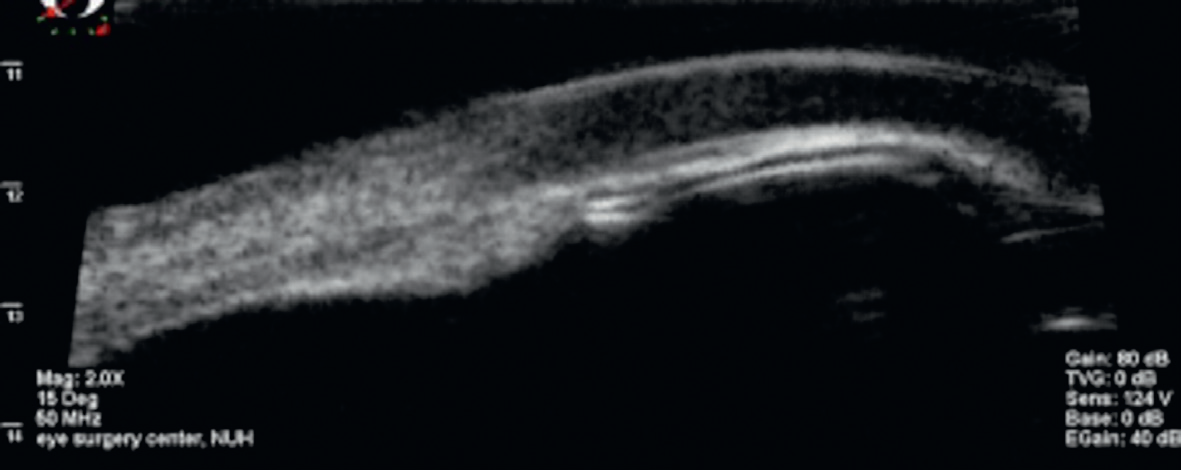

Malign glokom postoperatif birinci günde ortaya çıkabileceği gibi intraoküler cerrahiden yıllar sonra da ortaya çıkabilmektedir. İris-lens diyaframının öne hareketi sonucu hastalarda -8.0 diyoptriye varan miyopik değişim ortaya çıkabilmektedir. Pupil bloğundaki semptomlara benzer şekilde görme keskinliğinde azalma, oküler ağrı ve kızarıklık görülebilir. GİB seviyesine göre değişen derecede başağrısı, bulantı ve kusma gibi semptomlar eşlik edebilir. Biyomikroskopik muayenede ön kamara merkezinde daralma, patent iridotomi/iridektomi ve normal veya artmış GİB mevcuttur. UBM ile siliyer proseslerin öne rotasyonu gösterilebilir (Figür 2).

Figür 2. Malign glokomlu hastada UBM görüntüsü, siliyer cismin öne rotasyonu ve iridokorneal temas.